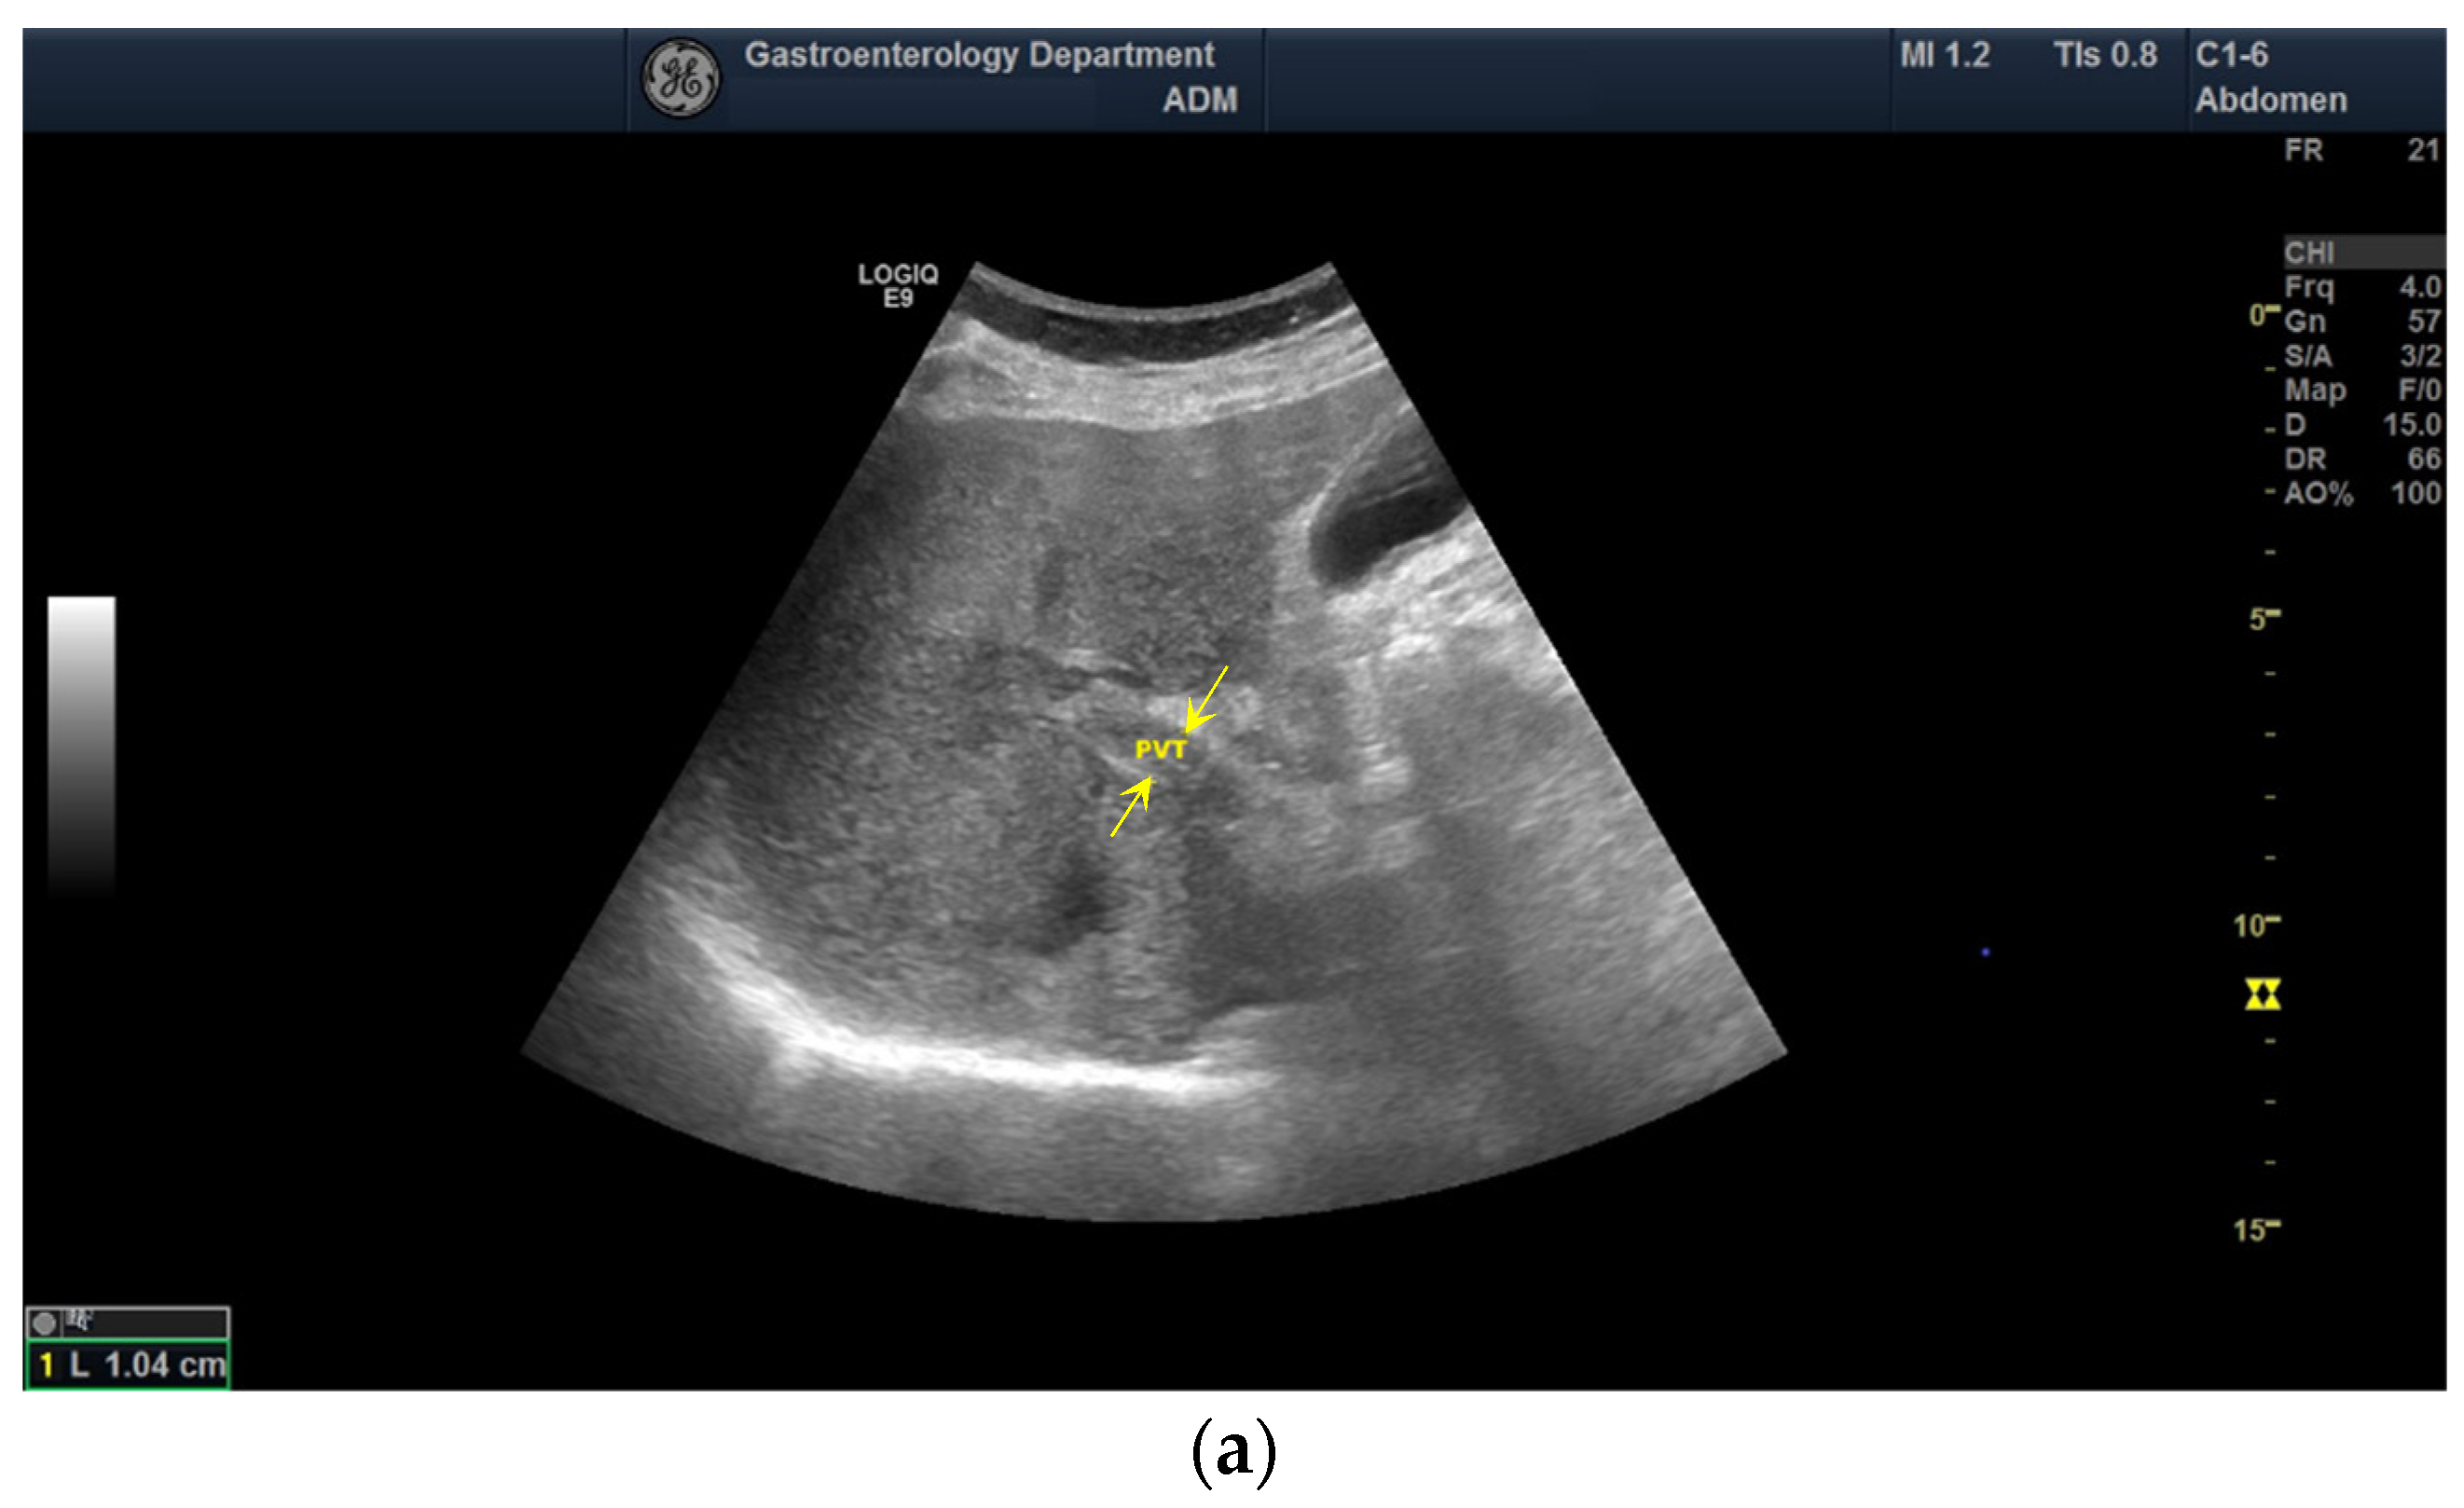

2.3. Diagnostic of PVT

3.5. The Performance of CEUS for the Characterization of PVT